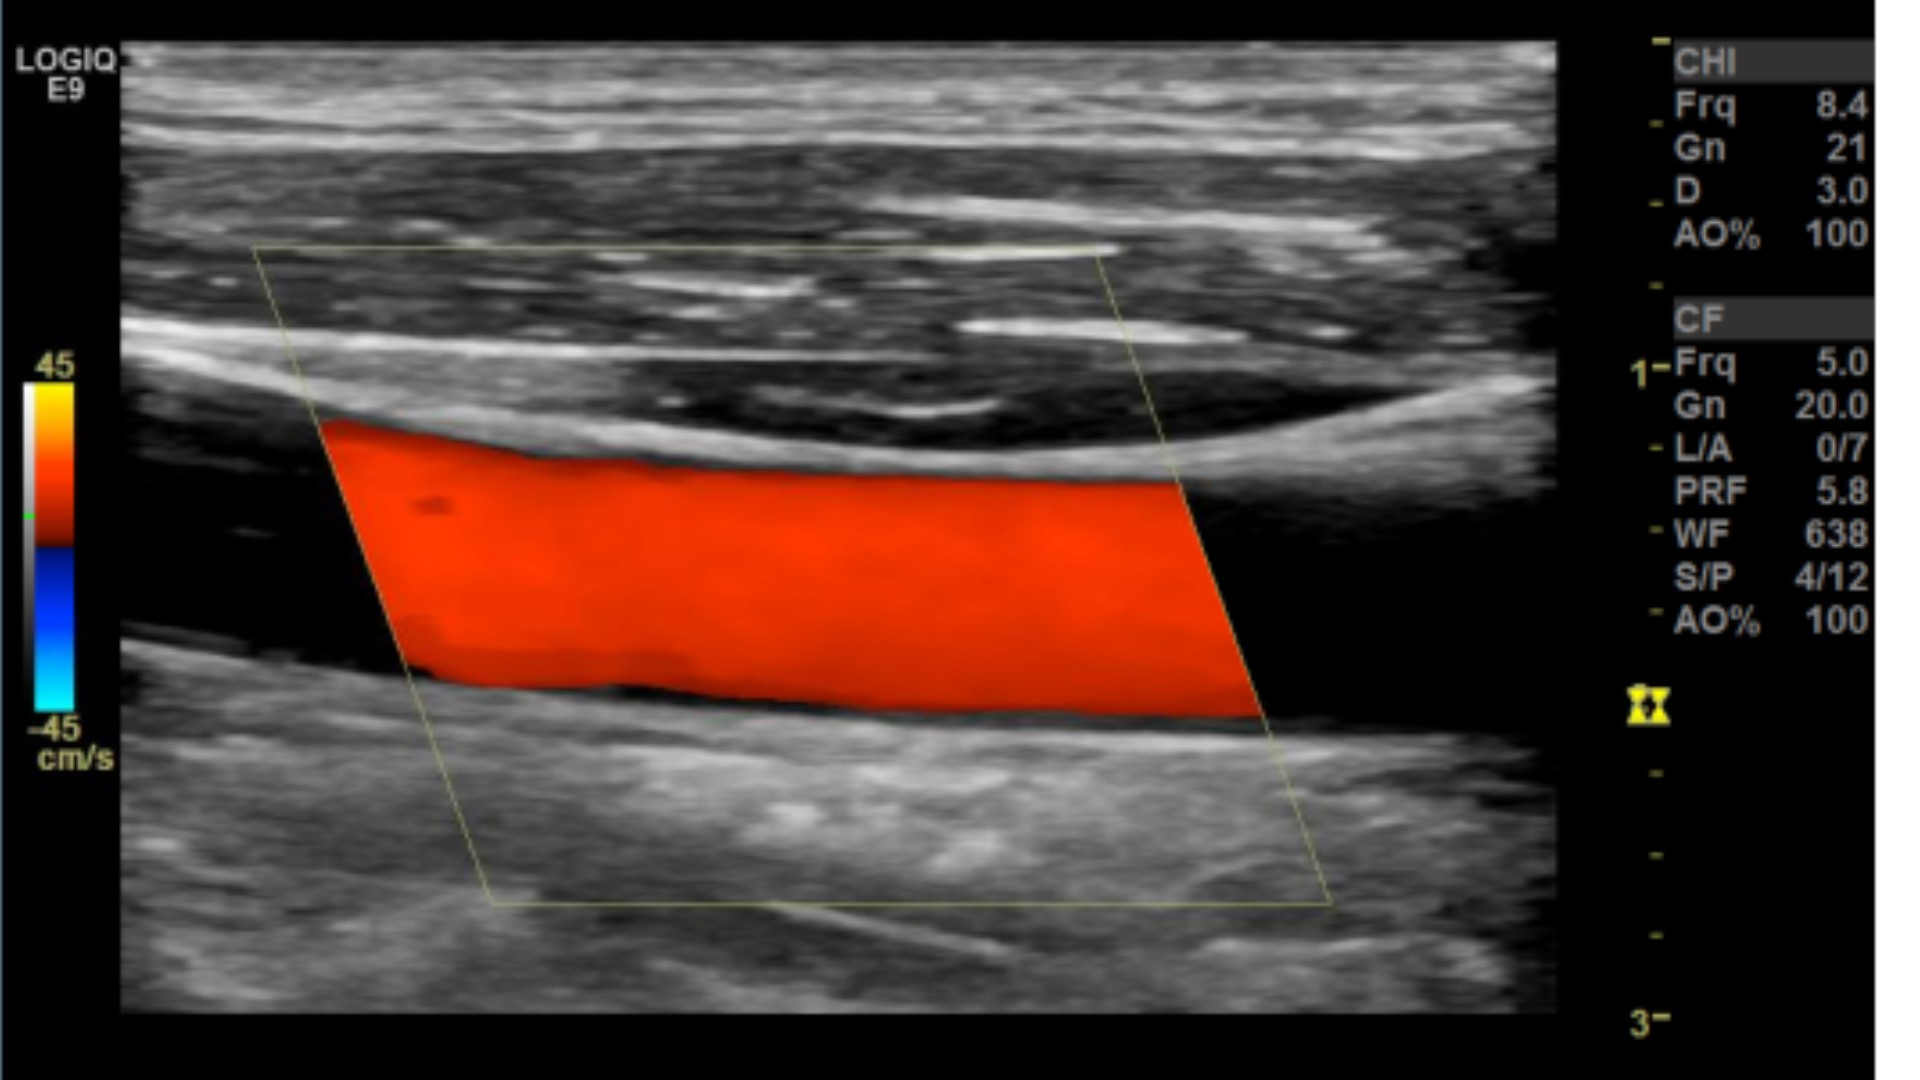

Taking technically superior images not only looks aesthetically pleasing, it is important in that it provides accurate data to render a correct diagnosis. A few parameters you may want to tweak are the doppler scale or pulse repetition frequency PRF and gain for both color and spectral doppler.

Optimal Doppler settings